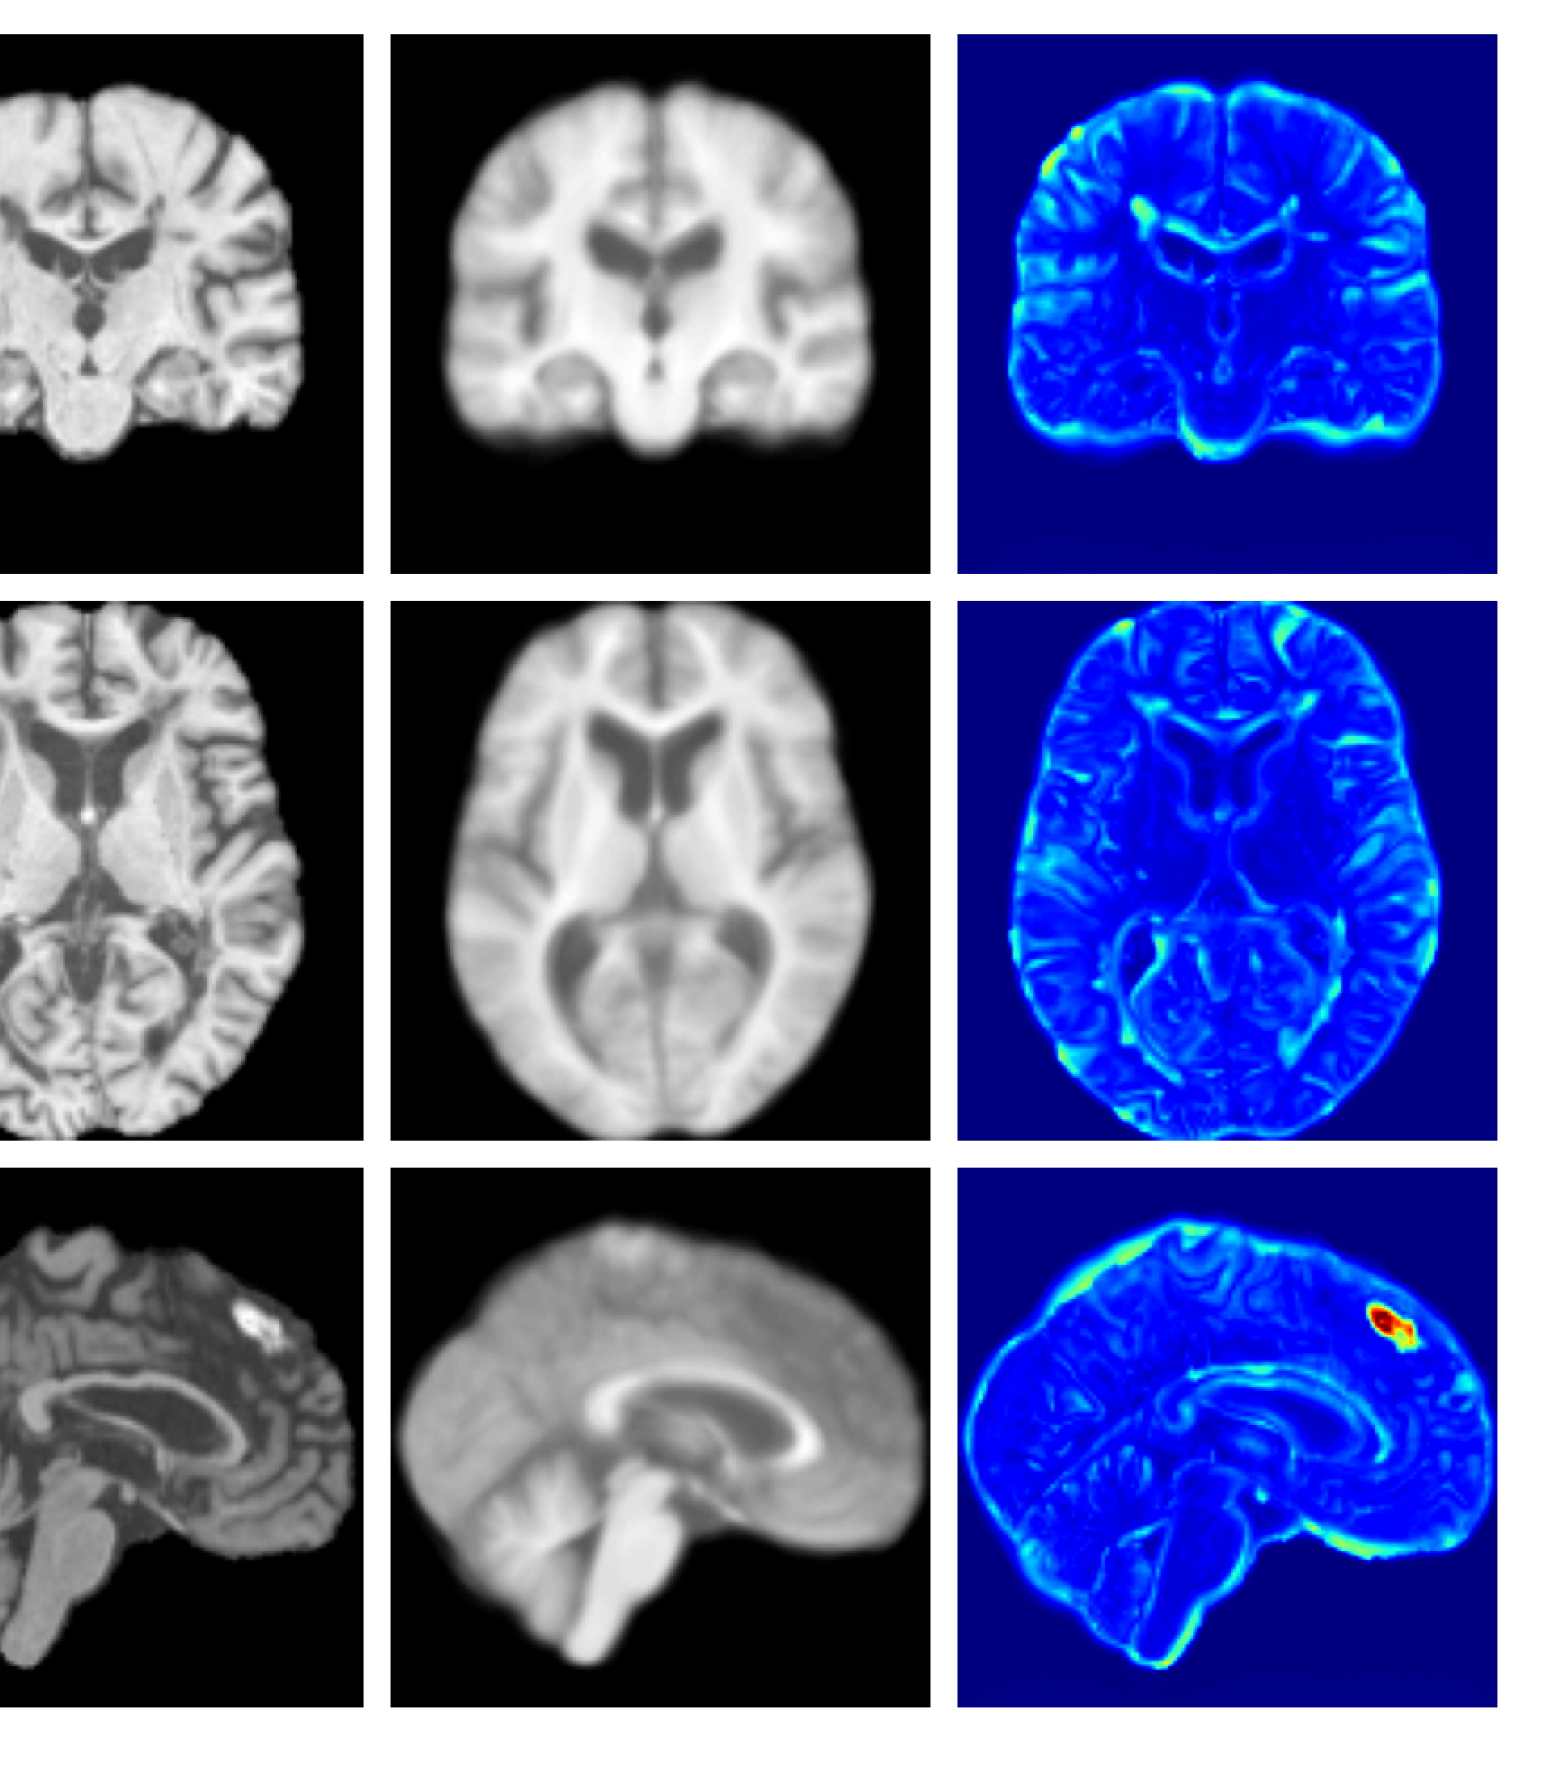

Figures 8 and 9 are enlarged versions of Figures 3 and 4 respectively, with the latter now including results from all compared methods. Figure 10 provides example reconstructions and anomaly maps for an AD subject from the ADNI disease cohort.

Figure 8: Enlarged example reconstructions and anomaly maps for a sample from the disease cohort of the UKBB dataset. Lesion and WMH are indicated in the original image by the red and yellow boxes respectively.

(h) CADD (Ours)

Figure 9: Enlarged example reconstructions and anomaly maps for a sample from the disease cohort of the XXXH dataset. The lesion region is indicated in the original image by the red box.